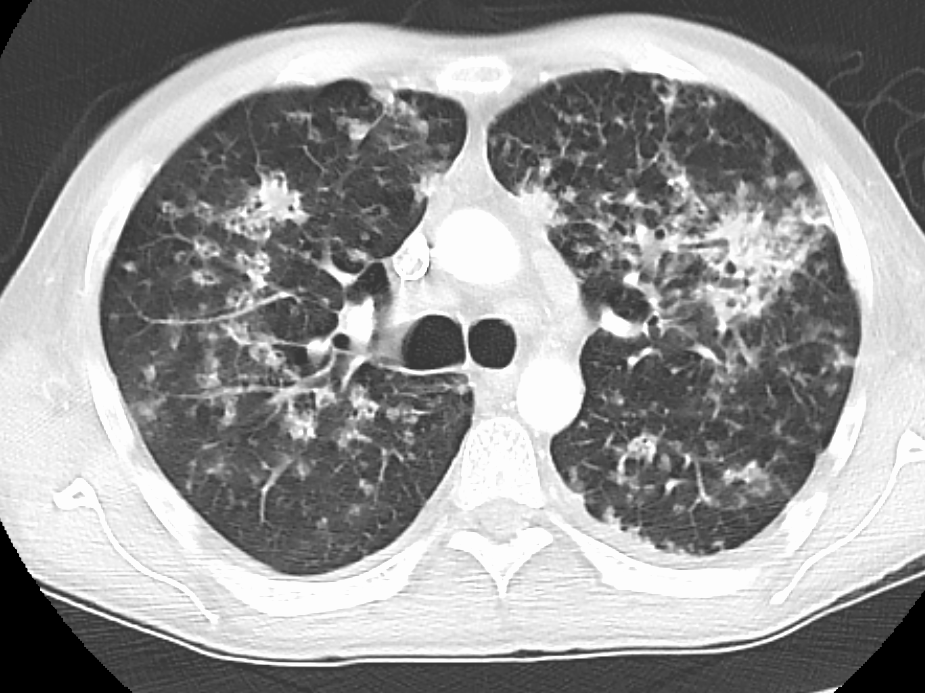

4. 진단

속립 결핵의 진단은 다른 형태의 결핵과 같은 방식으로 진행되지만, 확진을 위해 여러 검사가 필요하다.[4] 여기에는 흉부 엑스레이, 객담 배양 검사, 기관지 내시경 검사, 개방 폐 생검, 머리 CT/MRI, 혈액 배양 검사, 안저 검사, 심전도 검사가 포함된다.[10][22] 인터페론 감마 분비 검사(IGRA)라고도 하는 결핵 혈액 검사는 잠복 결핵을 진단하는 방법이다.[10]

드물게 폐암의 림프관 전파가 일반적인 흉부 X-선에서 속립 결핵 패턴을 모방할 수 있다.[15]